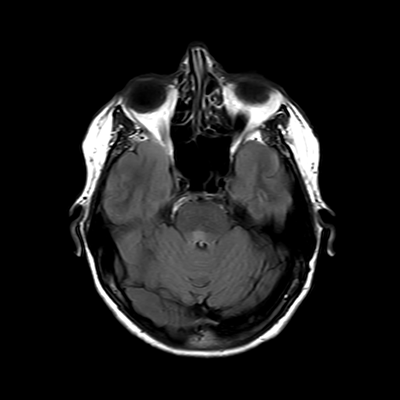

You also obtain an MRI of his brain once it's clinically safe to do so.

MRI brain (FLAIR)